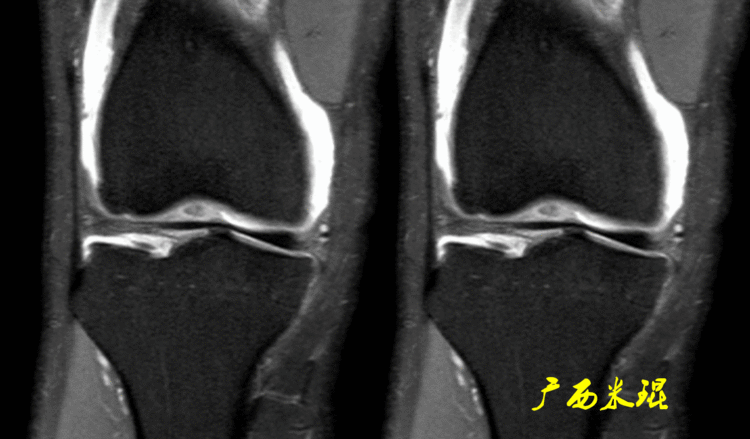

如同下面这张MR,左侧图像为手术前的,右侧图像为手术后的,术后病人疼痛等症状仍然存在,复查MR见外侧半月板前角分层,半月板前角的处理是有一定难度的,有经验的医生会考虑可能是手术者对前角的处理不够熟悉,没有通过另外的办法处理半月板前角的水平裂,不过也只能是猜测而已。所以,对于半月板术后的评估,症状的消失比MR重要!